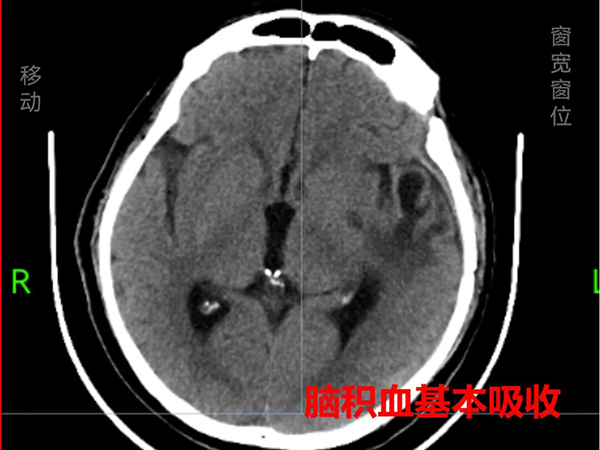

神经内科、神经外科与康复医学科接过救治的“接力棒”:一方面,予以脑保护、抗感染、抗癫痫、止咳化痰、营养支持等对症治疗;另一方面,采取渐进式呼吸肌训练、咳嗽排痰训练、肢体锻炼等综合训练。经过1个多月的系统治疗与精心护理,小周顺利拔除了气管插管和尿管,恢复了自主呼吸和言语功能,复查显示其颅内积血已基本吸收,脑中线复位,肺部感染也得到有效控制,并于1月28日顺利出院。